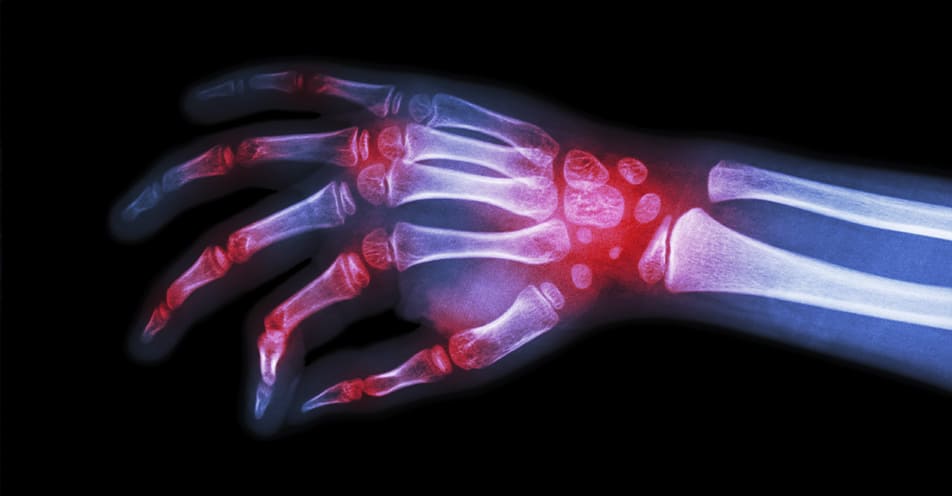

La prótesis de codo, muñeca e interfalángicas es un procedimiento quirúrgico que se realiza para reemplazar la articulación dañada en estas áreas. La razón más común para someterse a este tipo de cirugía es debido a la degeneración de la articulación, lo que puede causar dolor crónico y limitar la capacidad del paciente para realizar actividades cotidianas.

Además de la degeneración, las deformidades por secuelas de fracturas también pueden requerir la colocación de prótesis en estas articulaciones. Los pacientes con limitaciones de funcionalidad y un alto nivel de dolor en reposo y/o actividad también pueden ser candidatos para esta cirugía.

La colocación de una prótesis implica la eliminación de la articulación dañada y su sustitución por un implante artificial. Los implantes pueden estar hechos de materiales como metal, cerámica o plástico y pueden variar en tamaño y forma dependiendo de la articulación y las necesidades del paciente.